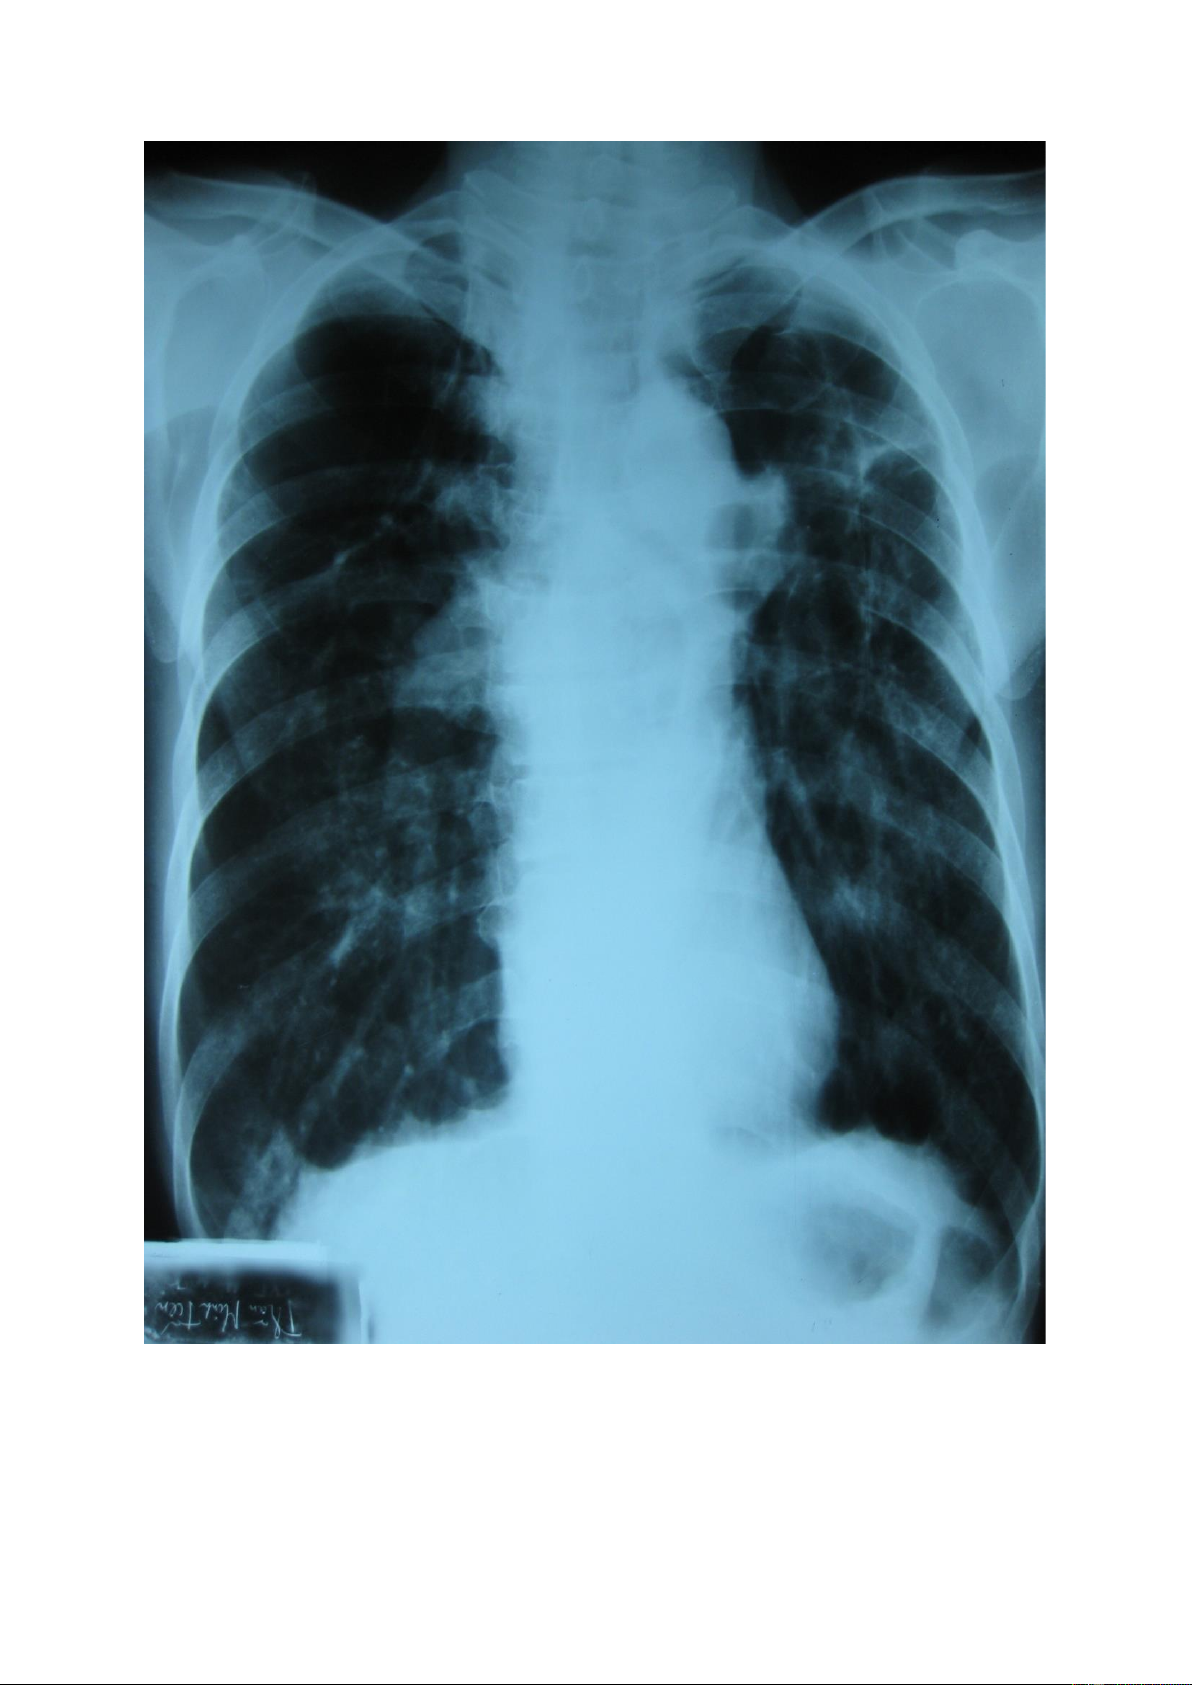

2. Tổn thương quá sáng

Là hình ảnh tổn thương có màu đen hơn mô phổi lành xung quanh. Nếu tổn thương có nhìn

thấy mạch máu đi qua chứng tỏ thuộc vùng mô phổi, nếu tổn thương sát với bờ ngoại vi phổi

không thấy phân bố mạch máu bên trong thường gặp trong tràn khí khoang màng phổi. lOMoAR cPSD| 22014077

2.1. Quá sáng vùng nhu mô lOMoAR cPSD| 22014077

2.2. Quá sáng do tràn khí màng phổi